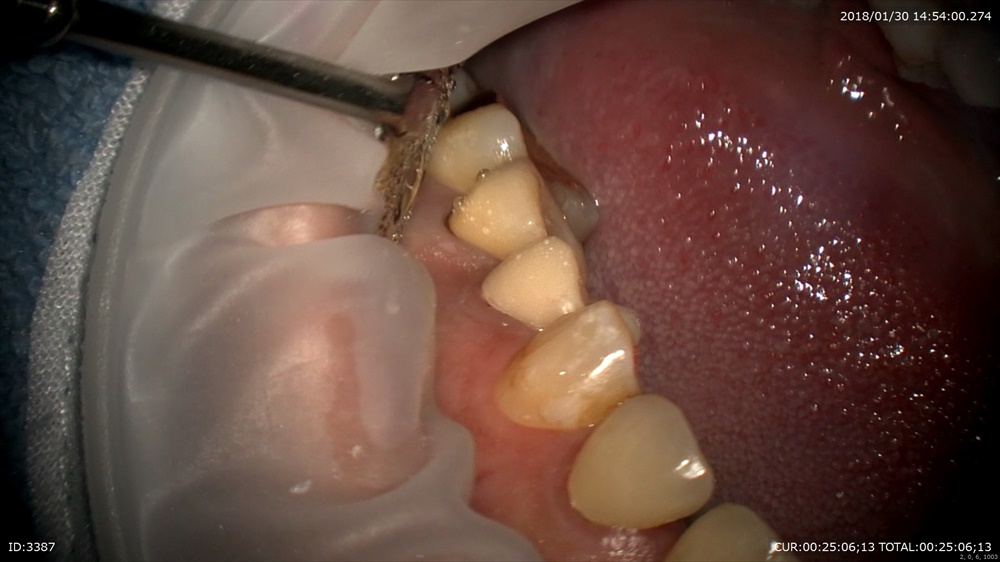

精密根管治療が終わると土台を立てます。

丁寧に削ります。

ここから仮歯を作りフィット

ガイドや形を与えます。

これで使用して問題なければ本物の型を精密に採るわけです。

だから仮歯が重要、形や大きさ、などあらゆる情報が入っています。当院で仮歯がない状態がないのはそのような理由からです。